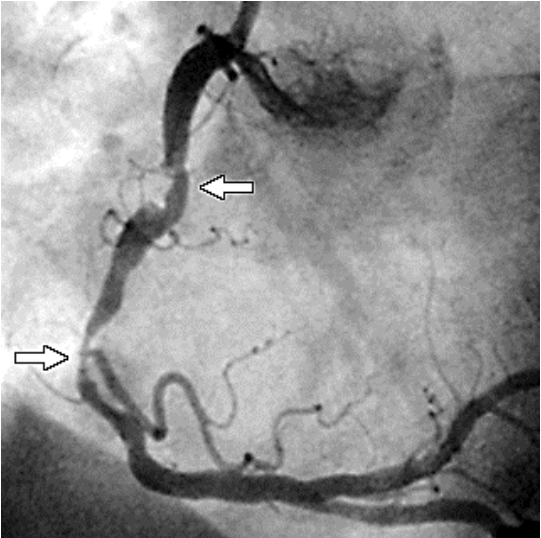

A imagem acima demonstra uma artéria coronária extremamente comprometida. De acordo com a imagem, é correto inferir que as setas indicam

Provas